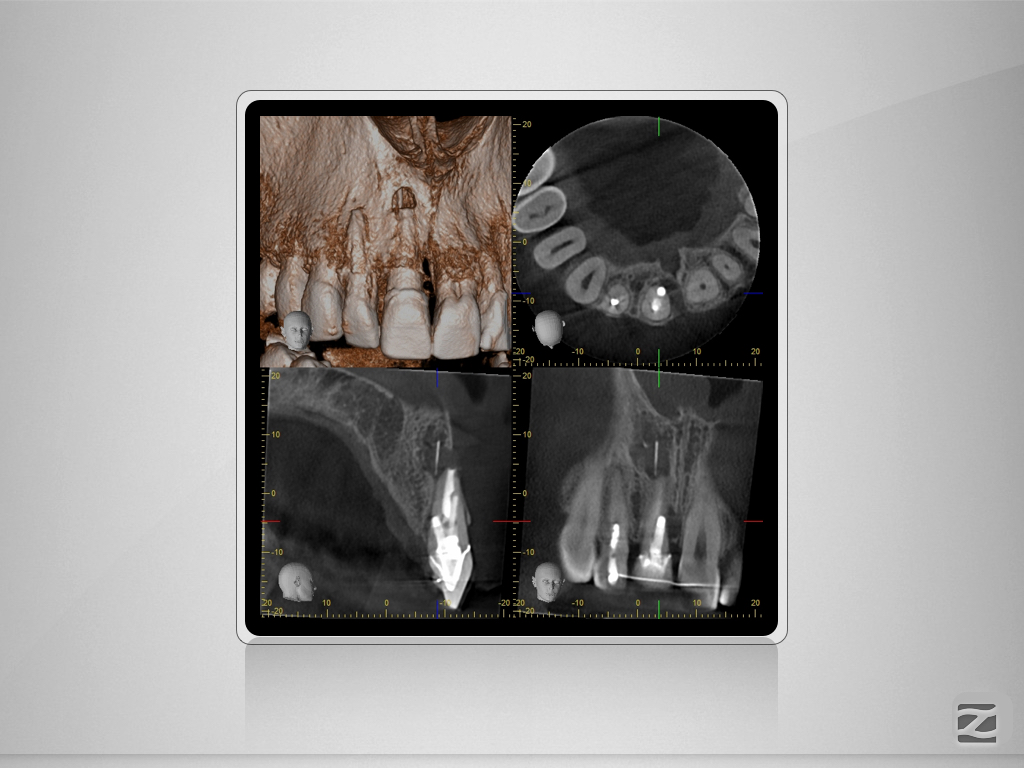

11D.003 Veröffentlicht 26. Oktober 2015 am 1024 × 768 in Saving hopeless Teeth – DVT gestützte Behandlungsplanung